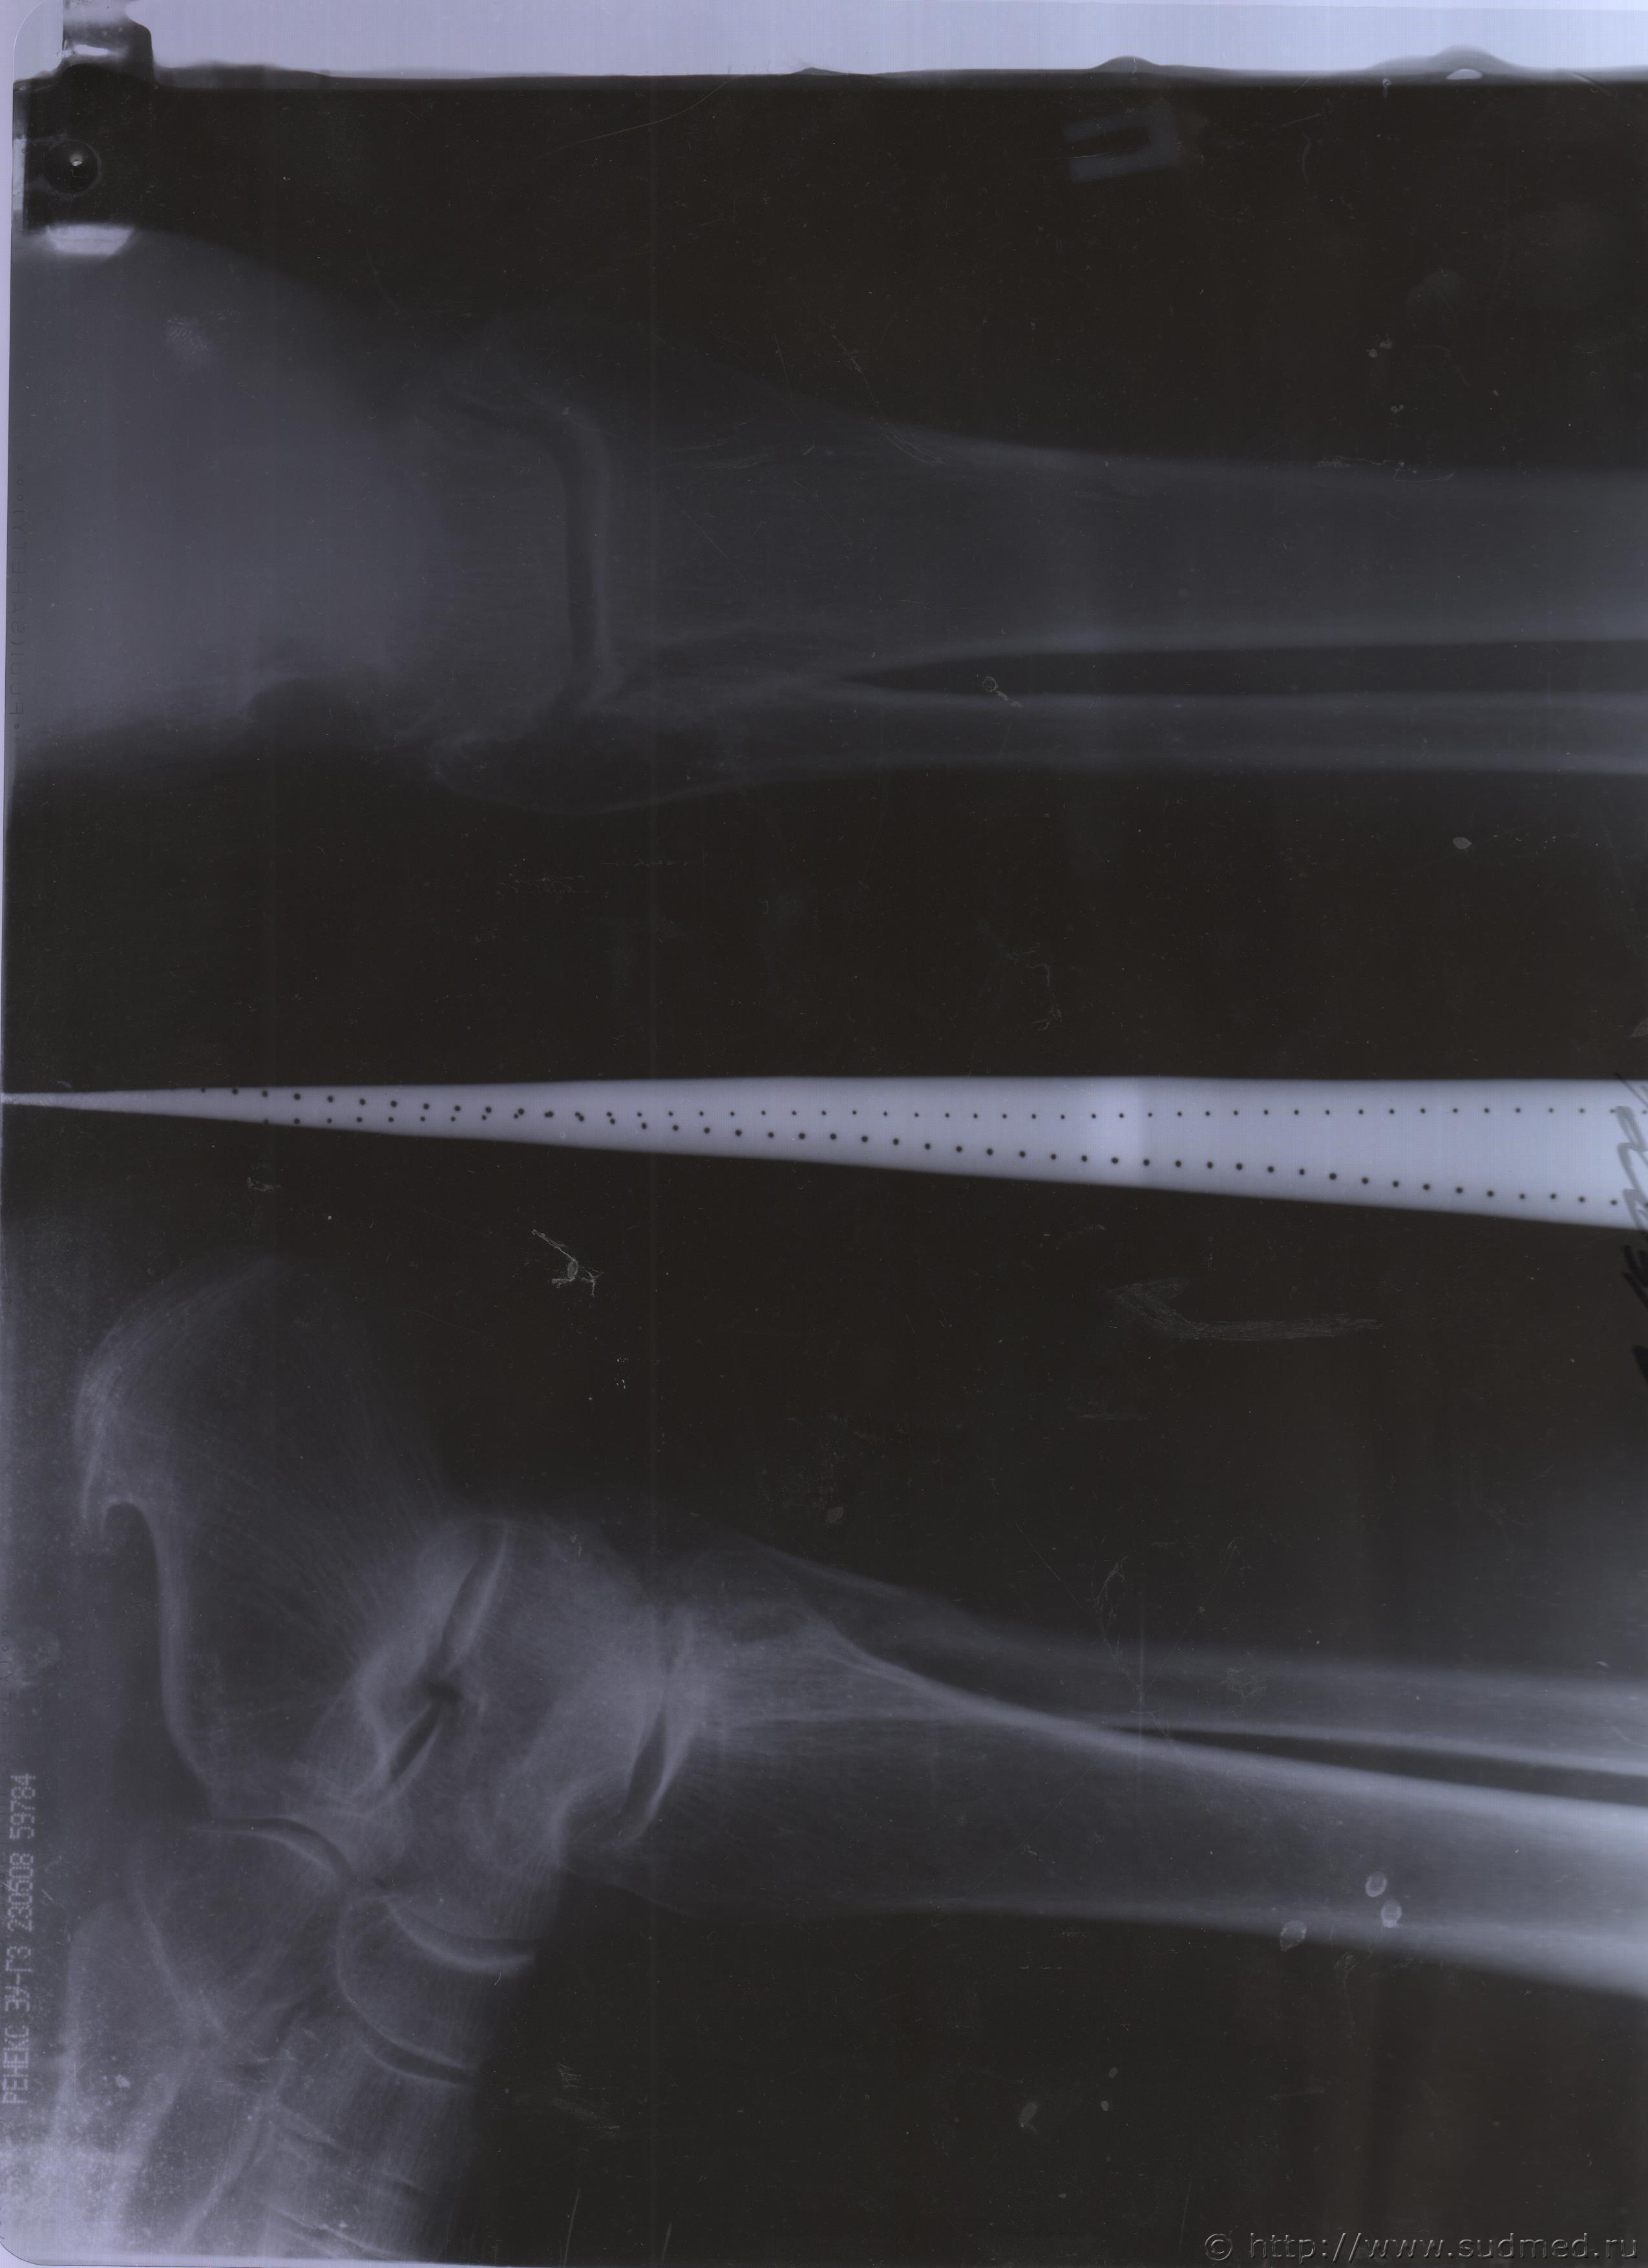

06.07.2015 г. при обращении в горбольницу мне выдали не описанный снимок( все рентгенологи были в отпуске) и справку № 4379 от 06.07.15 г. где диагноз: закрытый 2-х лодыжечный перелом правой голени без смещения. Копию справки прилагаю

За все 12 месяцев, что была на больничном, 8 раз делали снимки травмированной ноги и все заключения именно : «закрытый 2-х лодыжечный перелом правой голени без смещения».

После того, как был поставлен диагноз : «компрессионный перелом L2 позвонка поясничного отдела позвоночника». Амбулаторная мед карта, была украдена из кабинета врача травматолога. При восстановлении мед карты( в марте 2016 г.), врачом травматологом была взята копия справки от 06.07.15 г.из приемного отделения горбольницы. Справка № 4379 ( дубликат), диагноз : «закрытый 2-х лодыжечный перелом правой голени без смещения».

Посмотрите, это снимки за 12 месяцев.

Уважаемая Татьяна! По представленным Вами снимкам ничего сказать нельзя: нет маркировки даты каждого снимка (поэтому, невозможно их сравнивать друг с другом и соотносить с датой травмы), исследование непосредственно пленок гораздо более информативно, чем анализ представленных изображений (детали костной структуры в зоне перелома практически не видны).

Рекомендую проконсультировать все эти снимки у высококвалифицированного рентгенолога. Далее - по ситуации, т.е. в зависимости от его мнения. В любом случае, есть формальные основания для назначения дополнительной экспертизы, т.к., судя по представленному Вами фрагменту заключения эксперта, на экспертизу не были предоставлены все мед.документы с данными о лечении предъявляемой травмы (Вы пишете, что рентгенограммы делались на протяжении 12 месяцев, полагаю, что Вы и врачами наблюдались в течение этого срока, т.е. велась мед.карта).